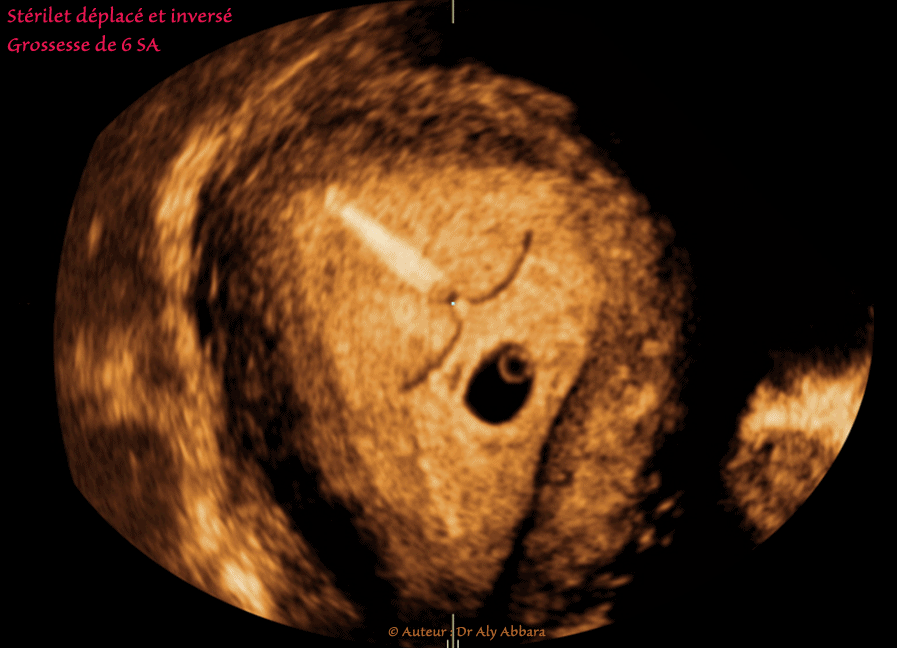

Grossesse intra-utérine évolutive de 6 SA (LCC = 5,2 mm). Echec de contraception par un dispositif intra-utérin (DIU) au cuivre, en forme de T, déplacé, inversé avec l’extrémité distale de sa tige verticale pointant vers la corne droite de la cavité utérine :

• Images échographiques montrant, sur une coupe frontale (coronale), un utérus normal, gravide, contenant au sein de son endomètre un sac gestationnel évolutif entouré par une couronne trophoblastique normale et renfermant un sac vitellin et un embryon de 5,2 mm de longueur crânio-caudale (6 SA) à activité cardiaque normalement présente.

La cavité utérine renferme également un dispositif intra-utérin (DIU) au cuivre en position anormale : inversion déplaçant l'extrémité distale de la tige verticale du DIU vers la corne droite de la cavité utérine.